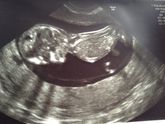

Всем привет! Вот и мой экватор, даже не верится… За это время я отменяю потихоньку утрожестан, съездили с мужем в Крым, маленький пинает меня во всю))) Вчера была на узи второго триместра, попалась ужасно *** узистка( даже и вспоминать не хочется((), … Читать далее